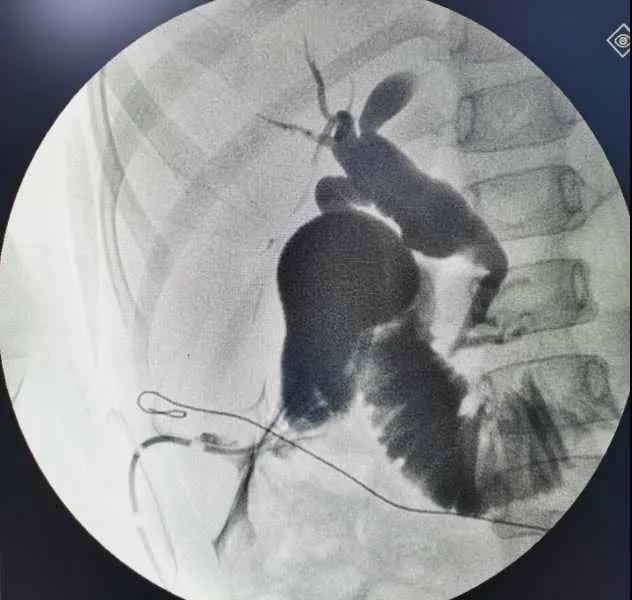

5月7日,西安國(guó)際醫(yī)學(xué)中心醫(yī)院小兒外科郭正團(tuán)教授團(tuán)隊(duì)成功為1名膽總管囊腫患兒進(jìn)行了腹腔鏡膽管造影 腹腔鏡膽總管囊腫切除 腹腔鏡肝管空腸吻合術(shù)。目前,患兒恢復(fù)良好,已正常進(jìn)食。

入院后,謝崇醫(yī)生積極為患兒完善術(shù)前準(zhǔn)備,MRCP(核磁共振膽道水成像)顯示該患兒為膽總管囊腫Ic型,有明顯的胰膽合流異常。面對(duì)復(fù)雜的病情,小兒外科郭正團(tuán)主任立即組織團(tuán)隊(duì)進(jìn)行術(shù)前討論,制定了完善的手術(shù)方案及應(yīng)急措施。

5月7日,一切準(zhǔn)備就緒,郭正團(tuán)主任主刀,帶領(lǐng)小兒外科團(tuán)隊(duì)進(jìn)行腹腔鏡膽管造影 腹腔鏡膽總管囊腫切除 腹腔鏡肝管空腸吻合術(shù)。術(shù)中,患兒膽總管與周圍肝動(dòng)脈及門(mén)靜脈粘連嚴(yán)重,給手術(shù)增加了難度。郭正團(tuán)主任沉著冷靜,操作嫻熟,完整剝離了膽總管囊腫及遠(yuǎn)端胰腺段膽管,肝總管與空腸完成了Roux-en-Y吻合,手術(shù)進(jìn)行順利。術(shù)后第2天,玲玲就可以下床活動(dòng);第6天,已正常飲食。